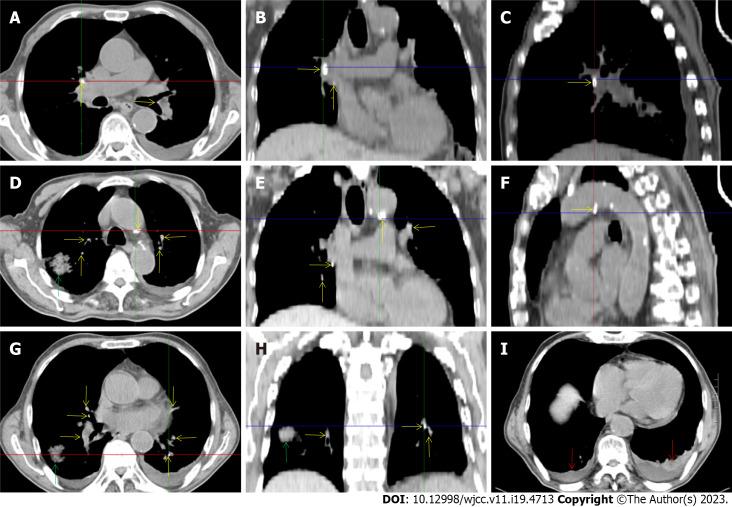

A 72-year-old male patient was definitively diagnosed with MDS with excess blasts-1 (MDS-EB-1) based on an increase in the percentages of myeloblasts and cluster of differentiation (CD)34+ hematopoietic progenitors and the identification of myeloid neoplasm-associated somatic mutations in bone marrow samples. The patient was treated with hypomethylation therapy and was able to maintain a steady disease state for 2 years. In the treatment process, the advanced MDS patient experienced an episode of progressive pancytopenia and bone marrow aplasia. During the aplastic crisis, the bone marrow was infiltrated with sparsely distributed atypical lymphocytes. Surprisingly, the leukemic cells disappeared. Immunological analysis revealed that the atypical lymphocytes expressed a high frequency of CD3, CD5, CD8, CD16, CD56 and CD57, suggesting the activation of autoimmune cytotoxic T-lymphocytes and natural killer (NK)/NKT cells that suppressed both normal and leukemic hematopoiesis. Elevated serum levels of inflammatory cytokines, including interleukin (IL)-6, interferon-gamma (IFN-γ) and tumor necrosis factor-alpha (TNF-α), confirmed the deranged type I immune responses. This morphological and immunological signature led to the diagnosis of severe aplastic anemia secondary to large granule lymphocyte leukemia. Disseminated tuberculosis was suspected upon radiological examinations in the search for an inflammatory niche. Antituberculosis treatment led to reversion of the aplastic crisis, disappearance of the atypical lymphocytes, increased marrow cellularity and 2 mo of hematological remission, providing strong evidence that disseminated tuberculosis was responsible for the development of the aplastic crisis, the regression of leukemic cells and the activation of CD56+ atypical lymphocytes. Reinstitution of hypomethylation therapy in the following 19 mo allowed the patient to maintain a steady disease state. However, the patient transformed the disease phenotype into acute myeloid leukemia and eventually died of disease progression and an overwhelming infectious episode.

Disseminated tuberculosis can induce CD56+ lymphocyte infiltration in the bone marrow and in turn suppress both normal and leukemic hematopoiesis, resulting in the development of aplastic crisis and leukemic cell regression.